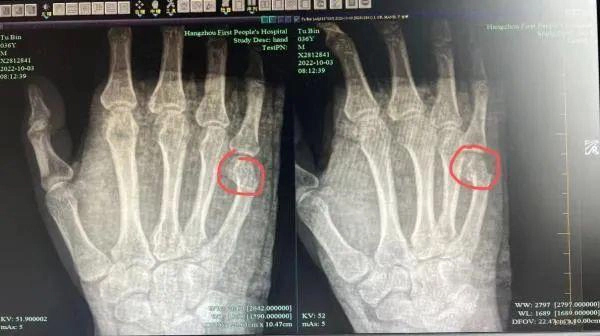

Theo kết luận của bác sĩ, anh Ngô bị gãy ngón tay út bên phải, phần gãy bị lệch rõ ràng cần nhập viện điều trị ngay lập tức.

Hình chụp X quang có thể thấy rõ phần xương ngón tay bị gãy của anh Ngô.